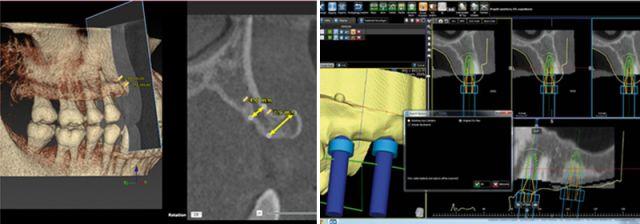

種植牙目前好選擇先進(jìn)的3D數(shù)字化全程導(dǎo)板種植牙技術(shù),根據(jù)數(shù)碼掃描,骨骼、神經(jīng)、血管等組織的三維模型重建,設(shè)計(jì)種植位置,選定合適的種植體,完全模擬顯示種植體在牙槽骨的位置,打印出導(dǎo)板模型,利用導(dǎo)板,確立種植體與牙頜竇底的距離、深度、種植體半徑、傾斜度等,按照種植導(dǎo)板導(dǎo)航種植,減少種植手術(shù)的時(shí)間,手術(shù)過(guò)程全程!華南目前在能開(kāi)展這項(xiàng)技術(shù)的醫(yī)院中德倫口腔首屈一指。